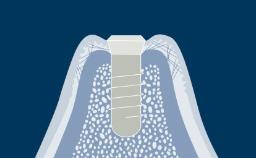

The moment when implants are put into function is marked by the connection of the implant prosthesis.

The choice of the most suitable loading protocol is an important step in the process of treatment planning. When selecting the moment of implant rehabilitation, you are faced with an important clinical decision.